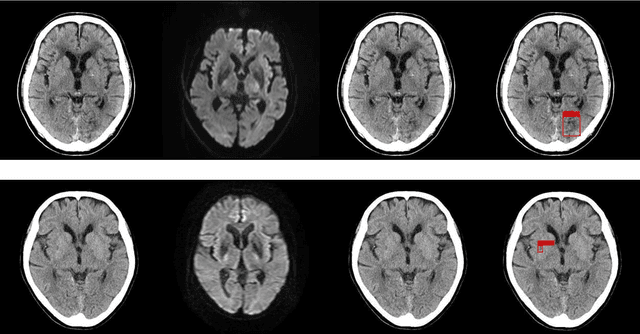

Abstract:Background and Purpose: We aimed to develop and evaluate an automatic acute ischemic stroke-related (AIS) detection system involving a two-stage deep learning model. Methods: We included 238 cases from two different institutions. AIS-related findings were annotated on each of the 238 sets of head CT images by referring to head magnetic resonance imaging (MRI) images in which an MRI examination was performed within 24 h following the CT scan. These 238 annotated cases were divided into a training set including 189 cases and test set including 49 cases. Subsequently, a two-stage deep learning detection model was constructed from the training set using the You Only Look Once v3 model and Visual Geometry Group 16 classification model. Then, the two-stage model performed the AIS detection process in the test set. To assess the detection model's results, a board-certified radiologist also evaluated the test set head CT images with and without the aid of the detection model. The sensitivity of AIS detection and number of false positives were calculated for the evaluation of the test set detection results. The sensitivity of the radiologist with and without the software detection results was compared using the McNemar test. A p-value of less than 0.05 was considered statistically significant. Results: For the two-stage model and radiologist without and with the use of the software results, the sensitivity was 37.3%, 33.3%, and 41.3%, respectively, and the number of false positives per one case was 1.265, 0.327, and 0.388, respectively. On using the two-stage detection model's results, the board-certified radiologist's detection sensitivity significantly improved (p-value = 0.0313). Conclusions: Our detection system involving the two-stage deep learning model significantly improved the radiologist's sensitivity in AIS detection.